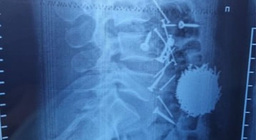

Хирурги в Самарканде провели экстренную операцию 29-летнему местному жителю, у которого в животе нашли более 200 граммов металлического крепежа.Бриф24